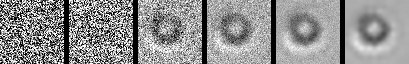

Image Generation. The image generation process begins with a sample of pure random Gaussian noise, denoted as . The goal is to progressively reverse the noising process, step by step, using the learned model to generate a realistic image. As shown in Figure 2, the model applies the learned denoising process starting from the random noise, iteratively refining the noisy image at each step to reconstruct the original data distribution.

At each step , the model predicts the denoised data from the noisy data by sampling from the learned distribution , as defined in the reverse process. This process continues until , at which point the generated data is a sample from the target distribution, resembling a clean image. The final result is an image that was generated from random noise, having gone through a series of denoising steps, guided by the reverse diffusion process learned during training.

Figure 2 provides a visualization of the denoising process in the reverse diffusion trajectory. Starting from pure Gaussian noise, the model progressively refines the image over 1,000 steps in our setup, gradually introducing particle-specific structures in a visually interpretable manner. To illustrate this process, we present six representative images along the trajectory. This progression highlights the ability of the generative model to recover subtle class-specific features, such as the halo effect in air bubbles or the smooth texture in silicone oil droplets, reinforcing confidence in the utility of these samples for downstream classification.